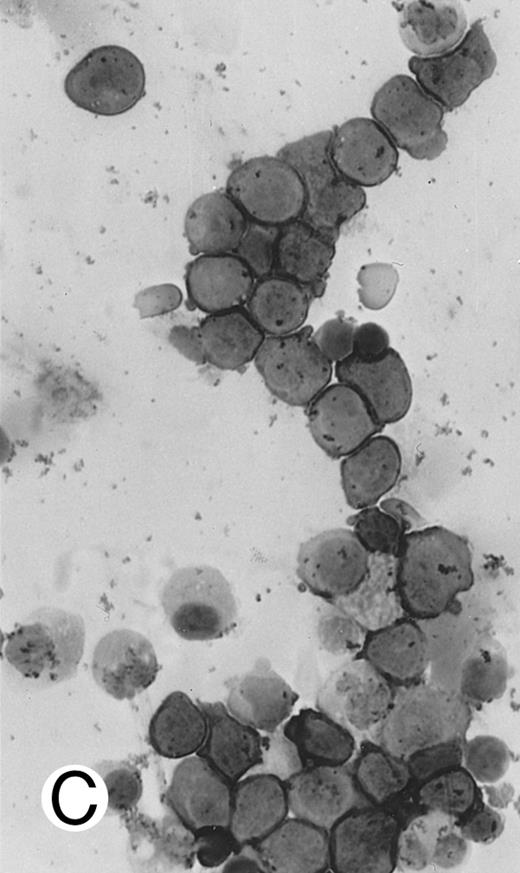

Aggressive NK cell leukemia/lymphoma (n = 5).These 5 patients were adults 37 to 54 years of age, with a mean age of 44.2 years and a median age of 41 years. They presented with fever and systemic symptoms and were found to have hepatomegaly, anemia, leukopenia, and thrombocytopenia (Table 2). Enlarged spleen was detected in 3 patients and enlarged lymph nodes in 2. Only 1 patient had skin rash. One patient had features of reactive hemophagocytic syndrome. The disease pursued a fulminant course, with rapid development of multiorgan failure. All 5 patients died within 6 weeks, some before a definitive diagnosis could be made or before treatment could be initiated. Postmortem examination was performed in 2 patients (cases no. 35 and 36), showing tumor involvement of multiple organs.

There were very few to numerous granular lymphocytes in the peripheral blood. Some of the granular lymphocytes were indistinguishable from normal large granular lymphocytes, with round nuclei, dense chromatin, and pale cytoplasm with fine azurophilic granules (Fig 5A). Some granular lymphocytes had larger nuclei with more open chromatin and distinct nucleoli (Fig 5B); occasional nuclei could show indentations. The azurophilic granules were sometimes large and coarse. There were also circulating normoblasts and immature myeloid cells. Marrow involvement ranged from subtle to extensive. In histologic sections, irrespective of site, there was a monotonous infiltrate of medium-sized cells with round nuclei and fairly condensed chromatin (Fig 6). Karyorrhexis was prominent. The infiltrate was diffuse, interstitial, or angiocentric.